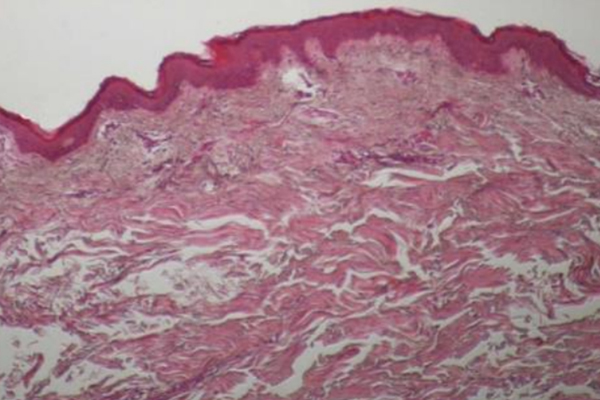

온다 시술 직후 피부조직